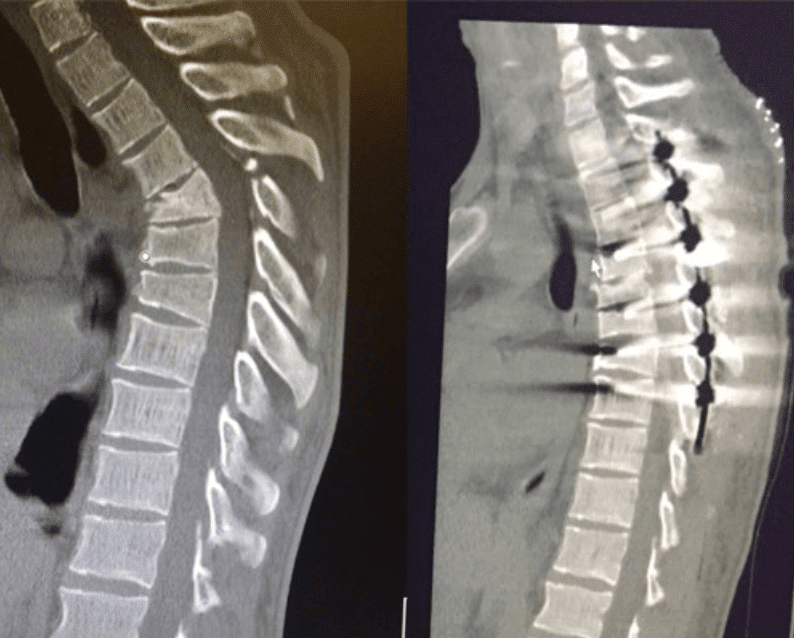

Luckily, the operation went great! Dr. Melamed and his staff did an amazing job fusing my T2-T8 and correcting the 40 degree kyphosis in my thoracic section of my spine. After a week in the hospital, my wife Georgia and I have spent the last 3 weeks resting at home.

Wednesday morning (04/12/17) Jimmy went into surgery with Dr Melamed in CA. The surgery lasted over 6 hours and 7 vertebrae were fused. The damage to the vertebrae was extreme and the surgeon did an amazing job re-breaking/aligning and fixing the spine. Everything went well, however getting the pain under control is the main focus as of the moment.

It will be 10 weeks before he will be able to start physical therapy, however, he is very lucky and blessed to have had a successful surgery. Thank you to everyone for all their love! X-rays and CT scans were done this morning to check everything is still all good, and will update when we know more.

After talking with Dr. Melamed with Disc MD Group in L.A, He had also agreed to the fusion but seemed genuinely concerned about my condition. He explained to me that I have a 30 degree kyphosis “A hunch back basically” in the Thoracic part of my spine. He went on to explain that by having the rods and fusion done of my back without the spinal Alignment done will have a terrible effect me in my quest to get back to living pain free. Not many surgeons are willing to do this surgery because it does involve breaking the spine even more to correct it. That being said, the possibility of being in better spine health than even before the injury excites me.